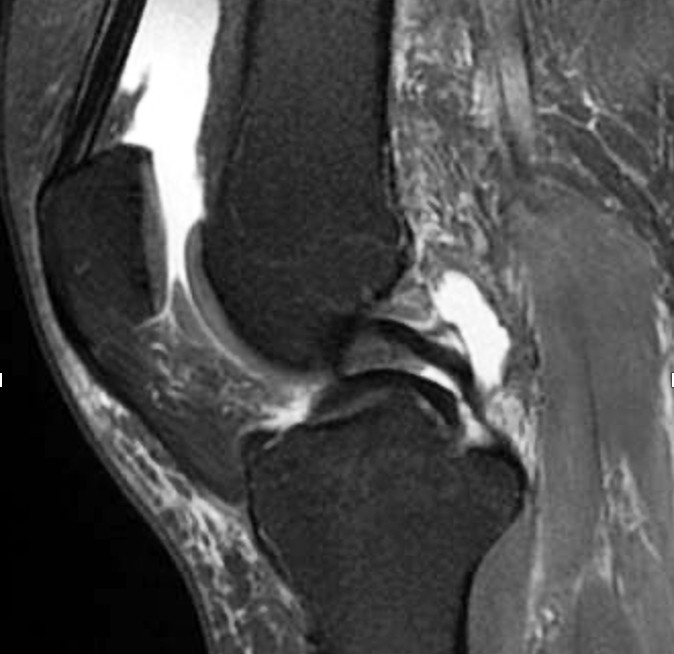

Traumatic meniscus injuries are most often seen in active younger individuals and are often high-energy injuries, not infrequently associated with damage to the anterior cruciate ligament (23). Typical traumatic tears are 'bucket handle'-shaped (longitudinal, vertical (Figure 2, Figure 3), and with the torn part of the meniscus potentially folded over towards the intercondylar eminence), radial, or flap-shaped. Folded bucket-handle tears can restrict both flexion and extension, and early repositioning and suturing are indicated to prevent shrinkage and destruction of the meniscus tissue.

Meniscal root tears are injuries at the site of or close to the posterior attachment of the menisci to the tibia (posterior root tears) (Figure 2) (24). Medial root tears are most often seen in degenerative knees as part of the development of osteoarthritis, and lateral root tears are most often seen in younger patients with damage to the anterior cruciate ligament. Root tears often cause more pain and effusion than other meniscus injuries.

Secondary MRI findings can include meniscal extrusion or associated bone marrow oedema (25). Extrusion occurs when the meniscus is either torn radially or close to the root (trauma) or stretched (degeneration) and thereby squeezed out of position in the joint. This leads to partial or complete loss of function of the meniscus – comparable to the effect of complete surgical resection (26). Meniscal extrusion is thought to increase the risk of rapidly progressive osteoarthritis (27).